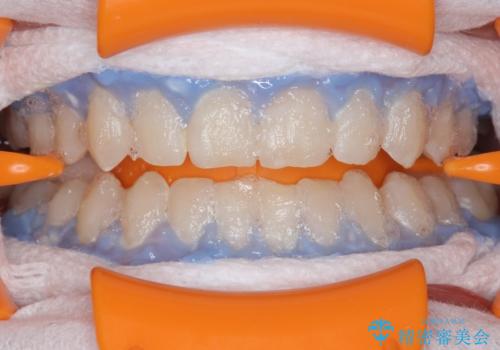

ホワイトニングエクセレントコースで3回照射の施術をしました。